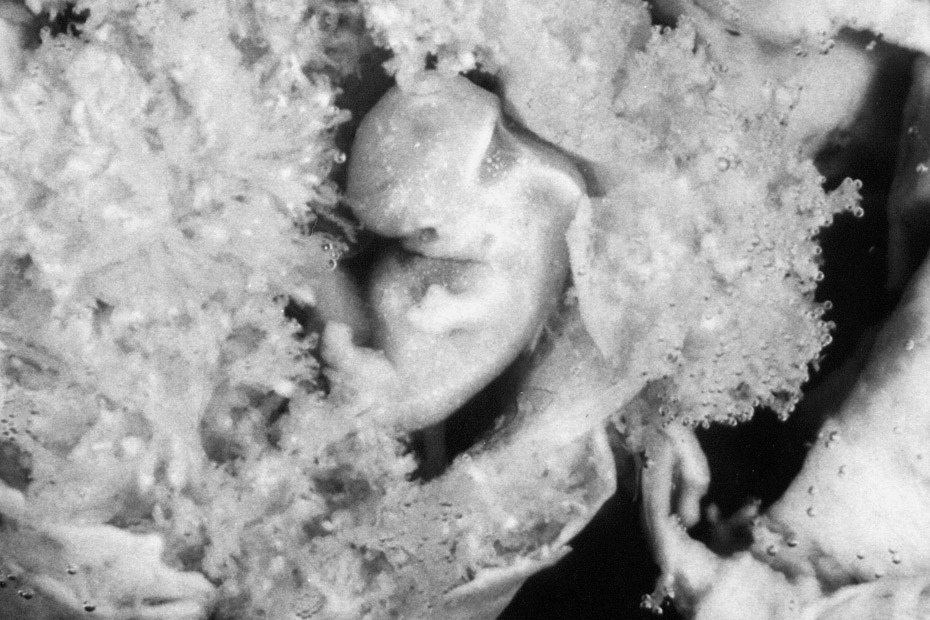

In every single developed nation today, preborn children, who fail to meet the arbitrary standards of their parents, are frequently exterminated in the womb. Among those who are systematically targeted are children who are diagnosed with Trisomy 21, more commonly known as Down syndrome.